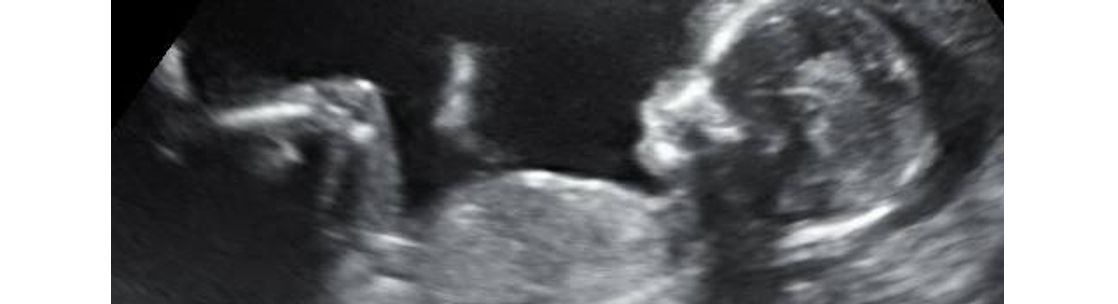

33 Weeks So Cute A Little Insight 3d 4d 5d Ultrasound Facebook